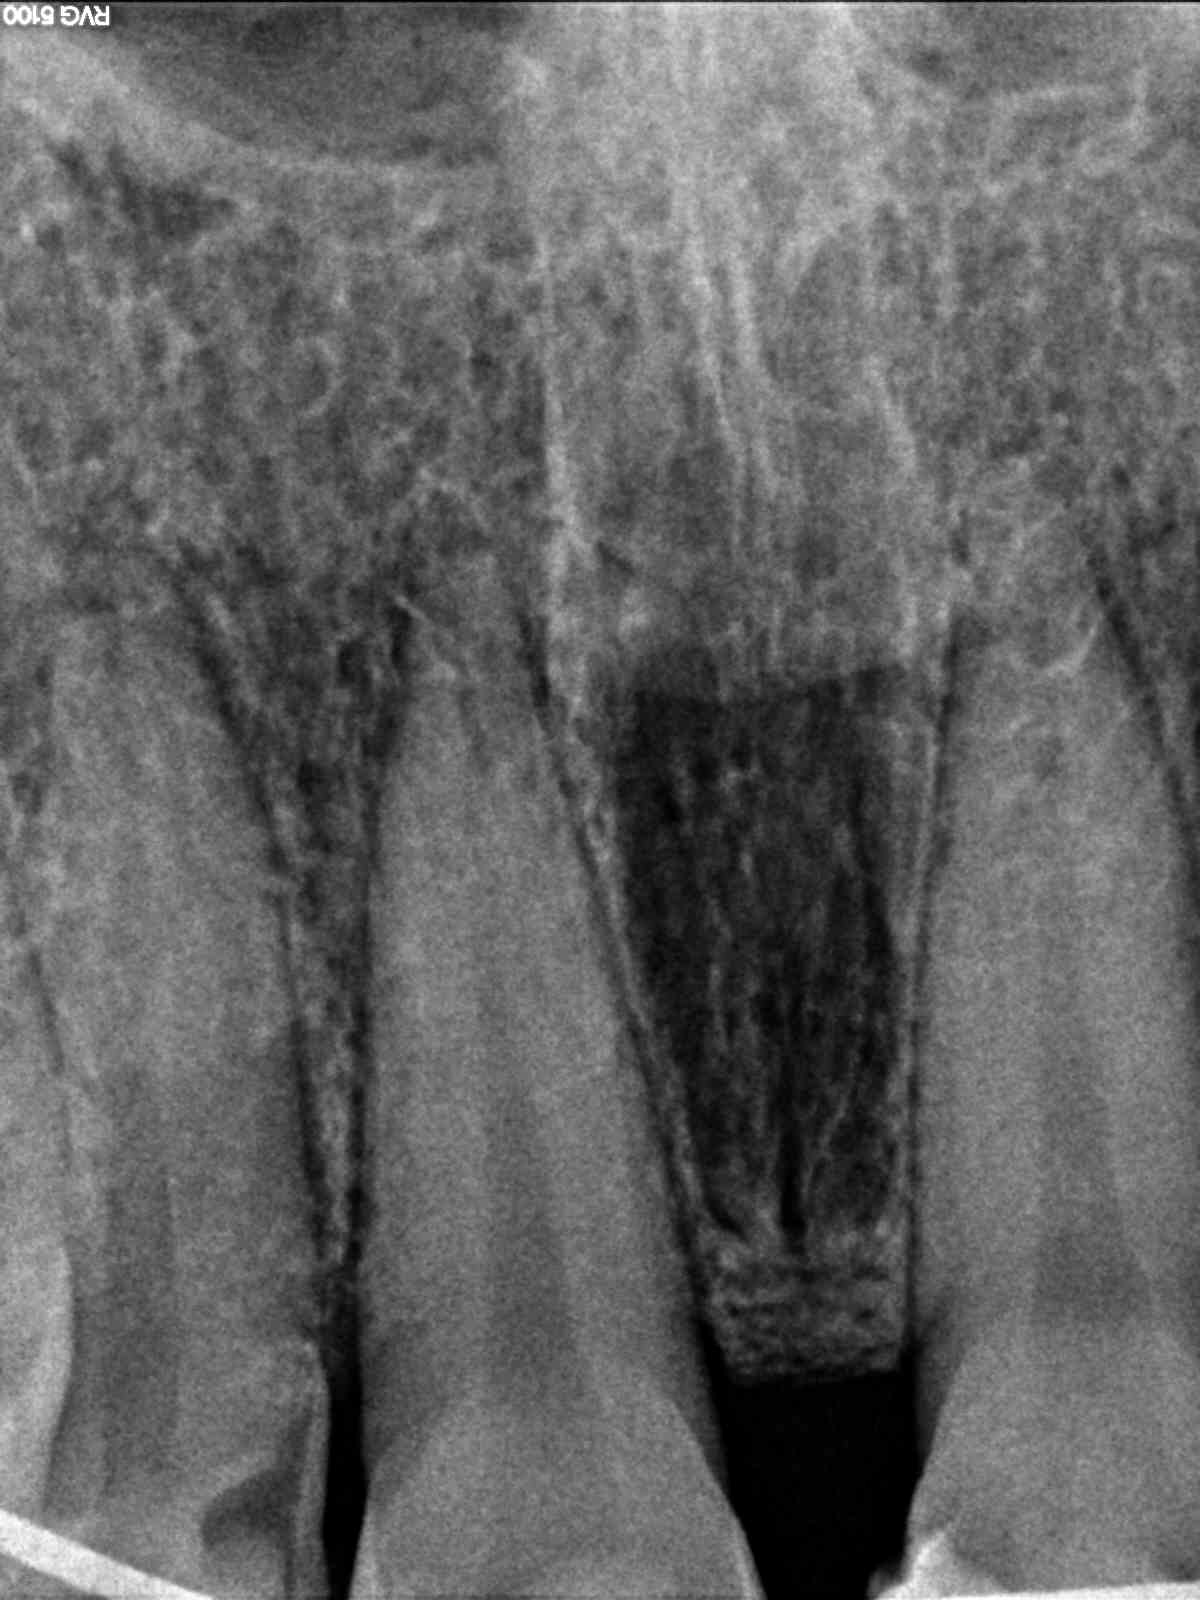

En tandarts dacht ook dat er breuk zit bij de wortelpunt bij de Middelste tand

V;g tandarts in the Philippines zit er bij de middelste aan de wortel een onsteking.

Graag advies ... vab wat er nu op de x ray te zien is

als ze last heeft en geen wortelkanaalbehandeling wil ondergaan in de Filipijnen kunnen antibiotica best tijdelijk helpen tot ze weer thuis is en haar eigen tandarts de situatie kan laten beoordelen. Lastig te zien op de foto of ze een ontsteking heeft of niet maar ik denk dat de filipijnse tandarts gelijk heeft en er inderdaad een ontsteking en breuk zit. Heeft hij een koudetest gedaan? Als ze geen kou meer voelt op die tand en de buurtanden wel dan zal'ie wel dood zijn.